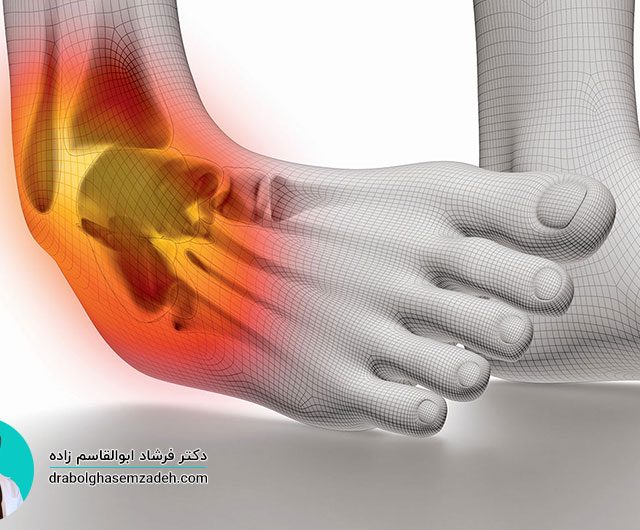

ورزشکاران و افرادی که در رشته های مختلف ورزشی فعالیت حرفه ای دارند، بیشتر در معرض خطر آسیب دیدگی مفصل شانه قرار دارند. مفصل شانه از اجزای متعددی تشکیل یافته است که آسیب دیدگی هر یک از اجزا، منجر به ایجاد اختلال در عملکرد درست شانه خواهد شد. پارگی کپسول مفصل شانه یکی از آسیب […]...